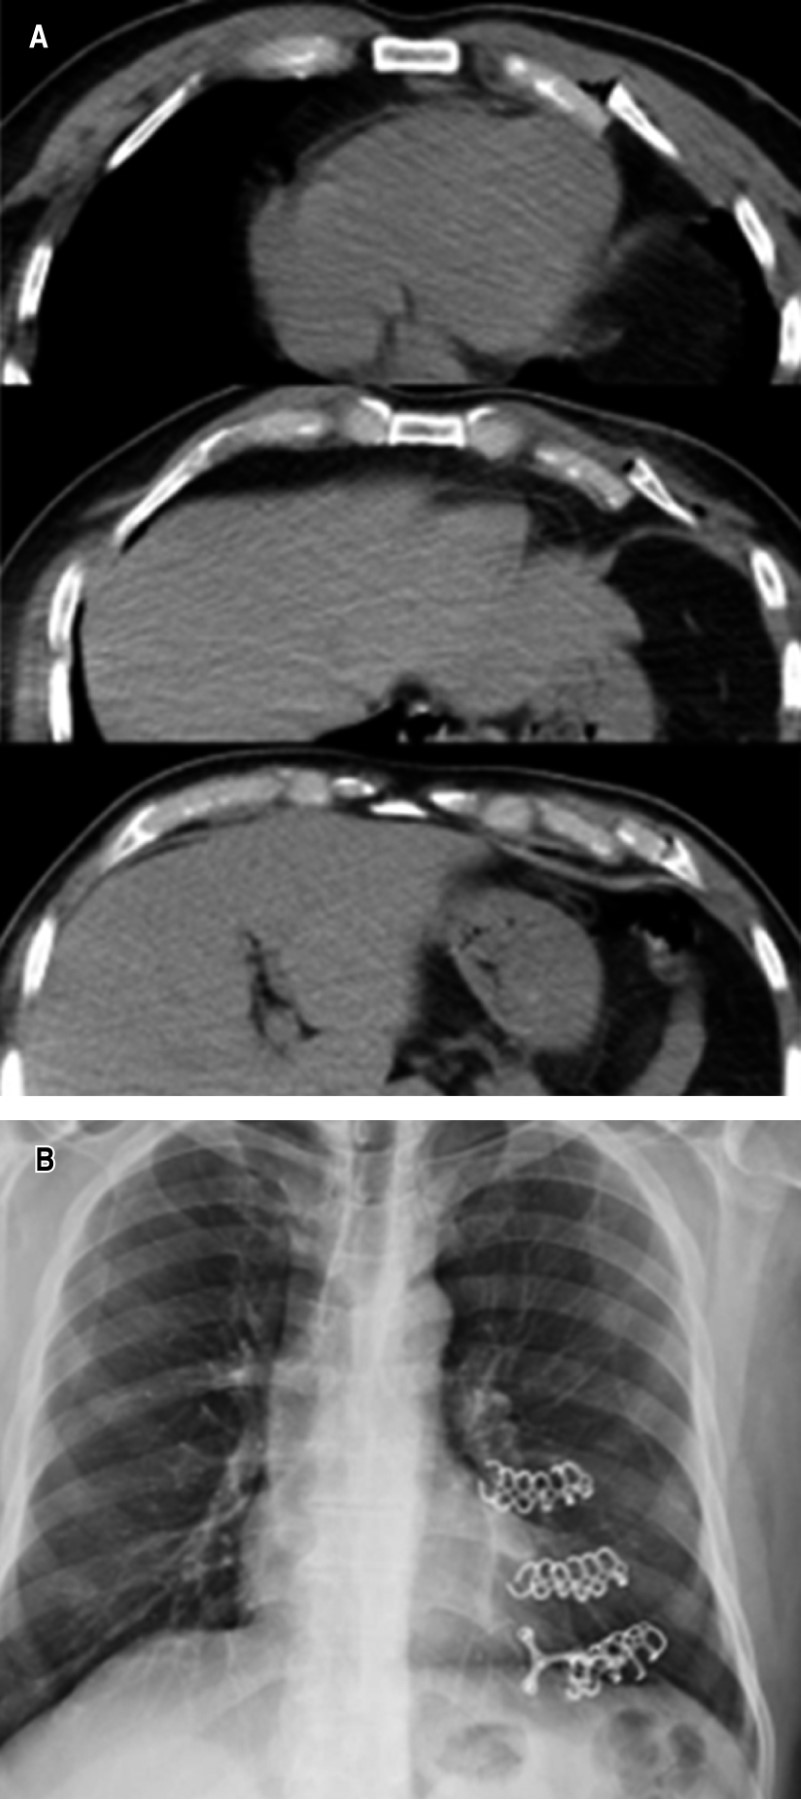

• ? Caso 2: femenino de 50 años de edad con tumor de segundo espacio intercostal derecho, el cual se resecó con bordes libres y se reconstruyó con sistema StraTos® y malla parcialmente absorbible (Figura 2).

Figura 2